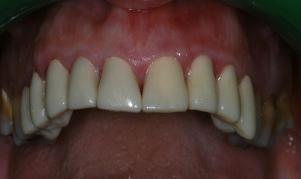

ΧΕΙΡΟΥΡΓΙΚΗ ΕΠΙΜΗΚΥΝΣΗ ΜΥΛΗΣ ΔΟΝΤΙΩΝ ΠΡΙΝ ΤΗΝ ΠΡΟΣΘΕΤΙΚΗ ΑΠΟΚΑΤΑΣΤΑΣΗ

ΜΕΤΑ